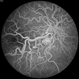

retinal arteriovenous malformations

David Emmert, Wilmer Eye Institute, Johns Hopkins University

Fundus camera

Fundus photographs and fluorescein angiogram of a 29-year-old male with asymptomatic racemose lesions characterized by direct artery-to-vein communication.